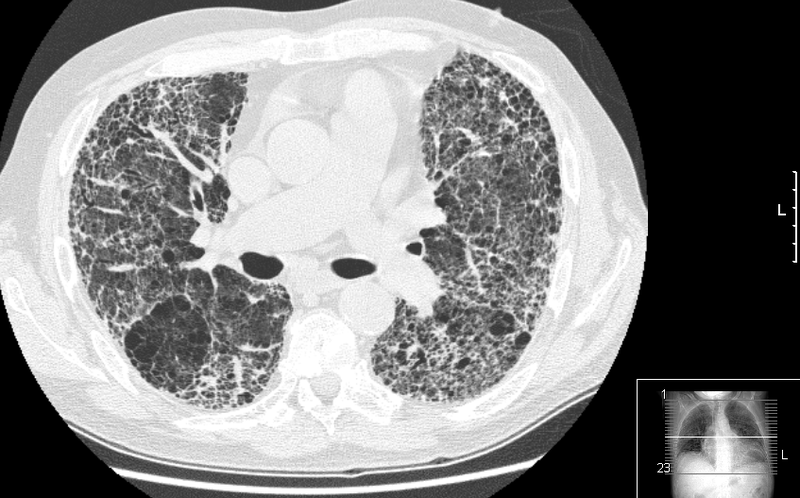

El aumento de peso en la edad adulta se relaciona con un mayor declive de la función pulmonar 28.02.2020 Con el paso de los años, la función pulmonar de las personas disminuye de forma natural

Localizan nuevos marcadores para el diagnóstico y pronóstico del cáncer de pulmón 27.02.2020 Científicos españoles han identificado algunas regiones repetitivas que en todos los pacientes y en todos los tipos de cáncer de pulmón estudiados tienen el mismo comportamiento